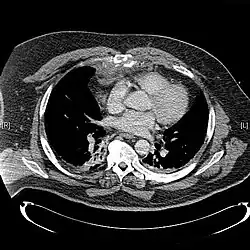

X-rays of the chest are taken in people with chest trauma and symptoms of sternal fractures, and these may be followed by CT scanning.[13] Since X-rays taken from the front may miss the injury, they are taken from the side as well.[14]